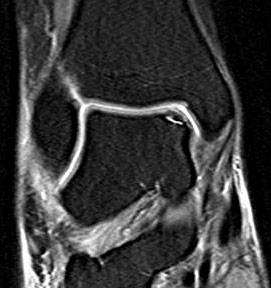

Abbildung 6 und 7, Video 2

Typischer Befund eines fibrotischen Faszikels (*), das zu einem Impingement am rechten lateralen Talus führt. Nach der Resektion des Faszikels ist der Blick auf das anterolaterale Gelenkeck zwischen der Tibia (Ti) und der Fibula (Fi) möglich.

Bei der intraoperativen Palpation mit dem Tasthaken zeigt sich die straffe Spannung des Faszikels und das mechanische Impingement an der lateralen Talusschulter. Oftmals finden sind entzündlich veränderte Synoviaanteile am Faszikel oder auch Schliffspuren am Knorpel der Taluskante.